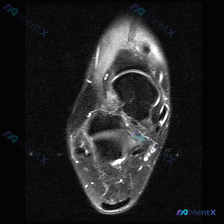

这是一张踝关节MRI轴位T2序列单帧图像,先给大家整理影像读片结果:

- 骨与关节:胫骨、腓骨远端形态正常,骨髓腔无异常信号,踝关节间隙清晰,未见骨质破坏、骨挫伤信号

- 韧带与肌腱:所有走行的肌腱韧带位置、信号都正常,没有腱鞘积液、信号增高或者撕裂表现

- 软组织:皮下脂肪和肌肉间隙清晰,没有看到明显软组织肿胀、弥漫性高水肿信号,也没有明显关节腔内大量病理性积液

整体读片结论:这一帧图像没有看到明确的异常病理改变。